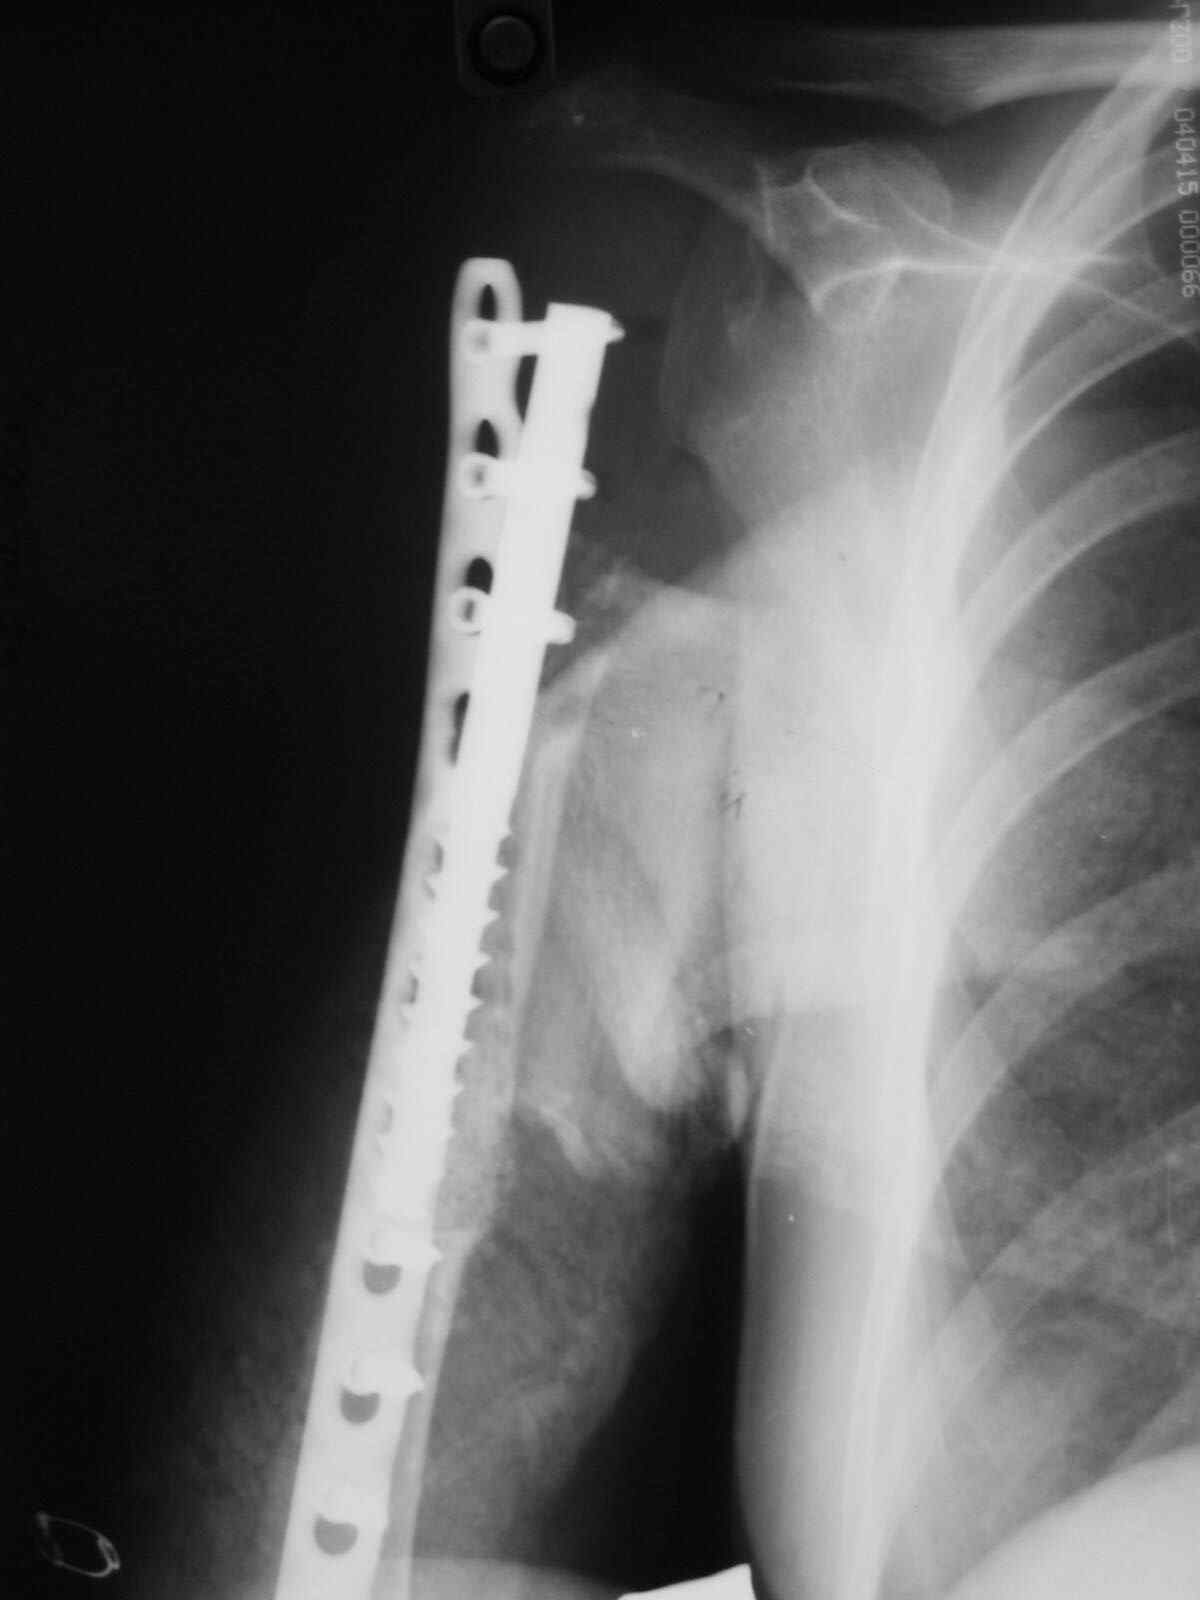

Больная 34 года операрована 14 лет назад по поводу литической формы ОБК головки плечвой кости

14 лет назад больной имлапнтирован протез плечевой кости выполненый по методике Воронцова на штифте-штопоре Сиваша,за 2 года до имлапнатации в онкологическом учереждении больной выполнена резекция проксимальоной части плечевой кости по поводу ОБК, ксенотрансплантации головки, и последующем его удалением на фоне гнойного процесса. У больной имелся втянутый обширный рубец и болтающееся плечо, афункциональная верхняя конечность, выраженный косметический дефект.П/опрационный период без осложнений, сохранялась выраженная контрактура в плечевом суставе, но стаилизация плеча и косметический эффект больную устраивал,даллее контакт с больной был утерян ( поменяла место жителсьтва. Через 14 лет полноценной жизни сельской жешщины ,больная нашла нас с клиникой выраженной нестабильности протеза. Категорически отказалась от замены протеза.

Выполнена операция- малоинвазивно проведена LCP пластина в образованный канал над головкой протеза, фиксирована к протезу и дистально к плечевой кости, на зоной резорбции трепонирована кость, удалена соединительно-тканная оболочка, полость заполнена chronOS. П/о период без осложнений, клиника нестабильность купирована. Прошло 2 года по телефону сообщила, что у нее все хорошо, продолжает жить счастливой жизнью сельской труженицы